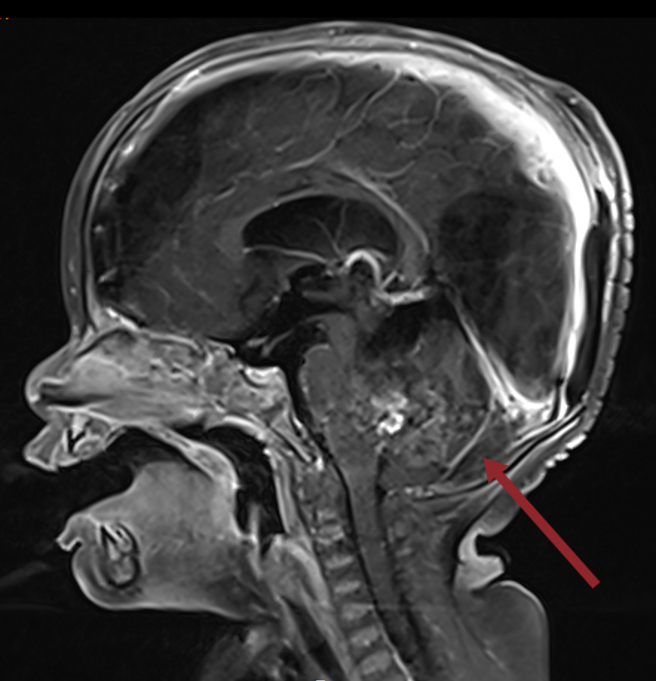

北医大台北癌症中心儿童脑瘤团队召集人黄棣栋指出,ATRT是非常罕见的恶性脑瘤,好发3岁以下幼童,台湾平均两年约两例;该名患者于去年8月确诊时仅9个月大,当时肿瘤几乎占满病童后颅窝的中央部分,必须分两次手术切除,幸好手术顺利,再搭配质子及药物治疗,目前恢復良好。

北医大附设医院放射肿瘤科主任李欣伦表示,幼儿的脑部在0至3岁间发展最迅速,接受放射治疗的年纪若越小或照射范围越大,5年内智商恐怕大幅下降,甚至连身高、视力、内分泌系统都会受到损害。质子治疗可有效精准打击肿瘤,同时闪避眼睛、脑部等健康器官组织。

黄棣栋强调,透过质子治疗有机会排除许多风险,对周边组织的保护效果也更好。观察该名婴儿在10月大时接受肿瘤质子治疗,是全球罕见案例,恢復状况不错,令人振奋。